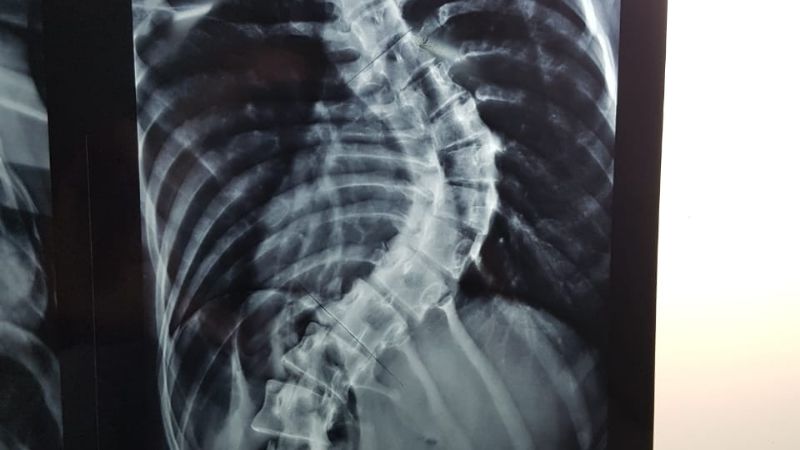

Durante el procedimiento realizaron la reducción de la desviación y fijación sobre un 80 por ciento de la columna vertebral –lumbar y dorsal-.

Tal como lo relatan los profesionales, esta clase de intervenciones se realizan, usualmente y a menor riesgo, en pacientes de edad temprana, antes que la malformación se agudice y los huesos ganen cierta rigidez. Sin embargo, en este caso, la paciente ya tenía 20 años de edad y una deformidad descompensada en su columna.

Nicolás Flores Kanter, médico que participó de la cirugía, explicó que “la intervención en sí misma llevó cinco horas en quirófano, fue compleja porque implicaba mucha pérdida de sangre; pero la paciente despertó bien y estuvo internada en sala durante 5 días, que era el objetivo del equipo de tratamiento. Ahora volvió para controles y se encuentra en perfectas condiciones, sin dolores, ni complicaciones, solo vino para que se le quitaran los puntos”.